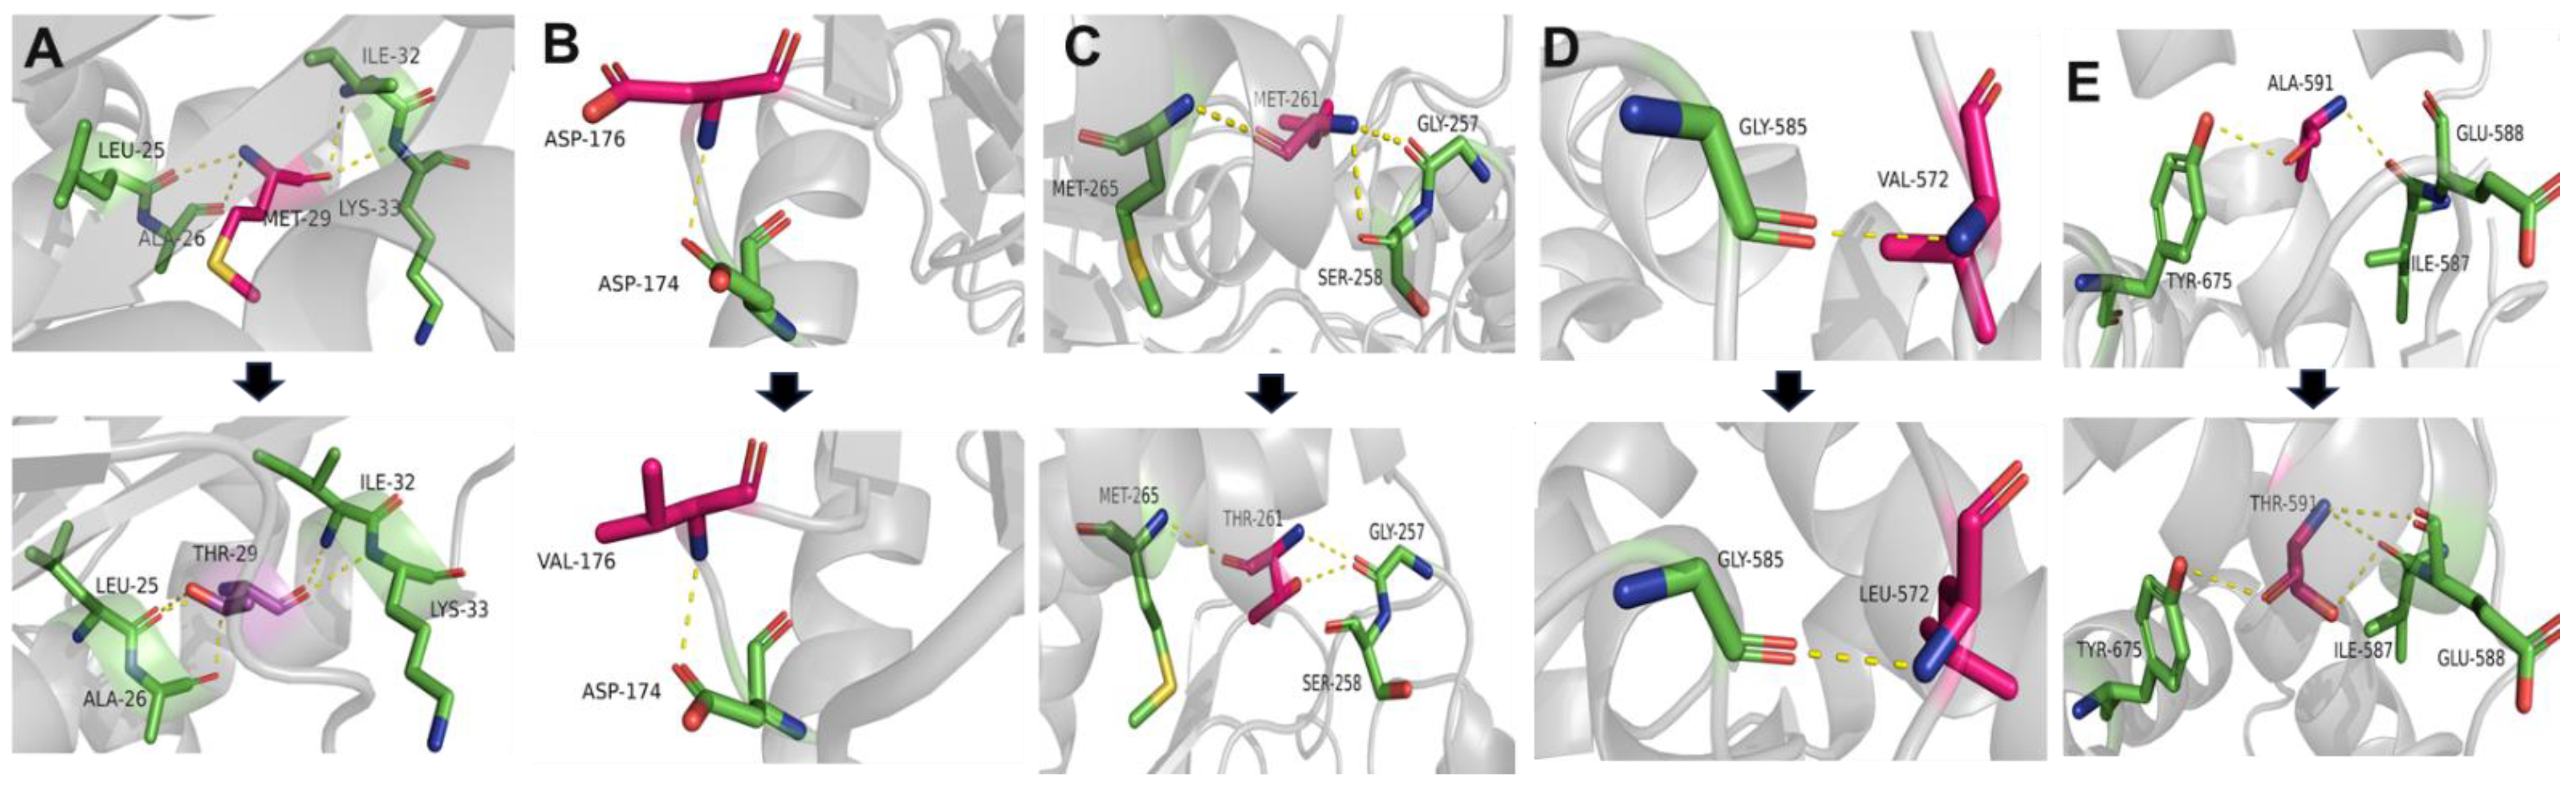

2.5. Conservation and Prediction of 3D Structural Changes of GNE Variants

3.2. Conservation Analysis and In Silico Prediction of the Mutation Effects